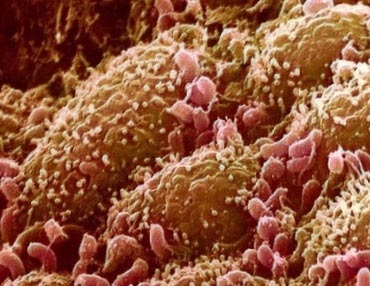

Fig. 6. Bacteriile din duoden (prezentate în roșu).